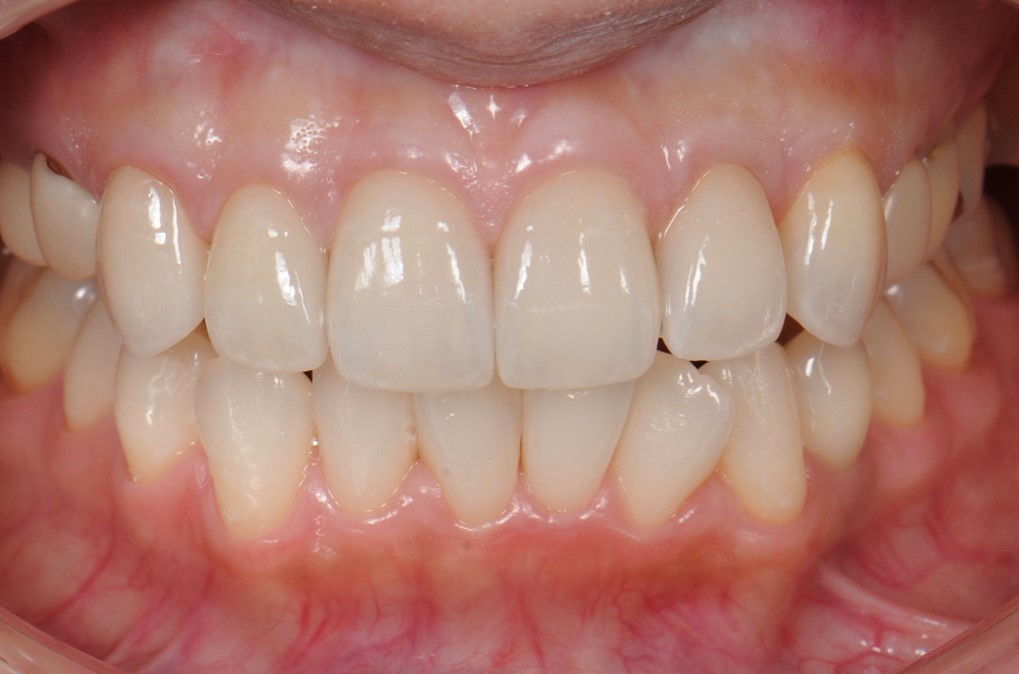

case2 症例(セラミッククラウン前歯)

治療前

治療後

| 費用(税込み) | 154,000円 |

|---|---|

| メリット・デメリット | デメリット 歯質を削合する必要がある |

| 治療回数 | 4-6回(根管治療は別) |

| 主訴 | 変色が気になる |